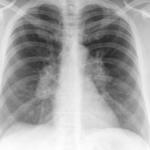

Signs

Album: Signs

Date: 04/28/2014

Size: 29 items

Views: 66701